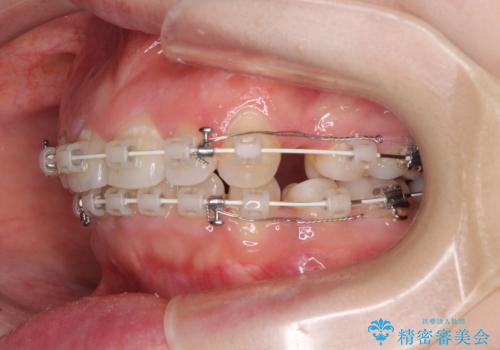

- 矯正装置

- 審美装置

元々上下正中の位置はずれていましたが、治療中によりズレが大きくなったので、元の位置に戻すため治療期間を余計に要しました。

横顔の印象が大きく改善され、患者様には大変満足していただきました。